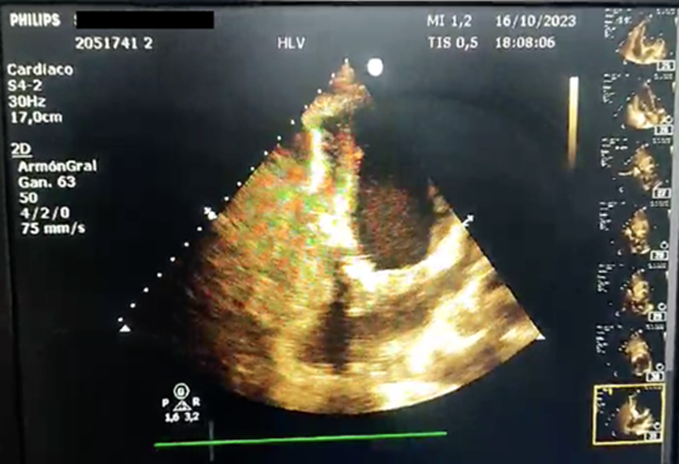

Aproximadamente 3 Semanas posterior al alta presenta cuadro de insuficiencia respiratoria asociado a insuficiencia cardiaca descompensada por lo que acude a nuestro Hospital de Especialidades Abel Gilbert Pontón siendo internada en Unidad Coronaria, a su ingreso se evidencia dolor precordial y torácico bilateral que irradia a región dorsal acompañado de disnea clase funcional NYHA IV/IV, tos persistente y edema leve de miembros inferiores, los laboratorios realizados evidencian anemia leve con hb 10.8 g/dL, péptido natriurético elevado de 12895 pg/ml, enzimas cardiacas negativas, hematuria y proteinuria en uroanálisis; en la radiografía de tórax se muestra cardiomegalia y derrame pleural bilateral; En electrocardiograma taquicardia sinusal, dextrorrotación, complejo QS en cara inferior, sin alteraciones de la onda T y segmento ST. En eco de pleura muestra derrame pleural derecho de moderada a gran cuantía y derrame pleural izquierdo moderado, sospechando de colagenopatía vs enfermedad autoinmune a descartar. Se realiza ecocardiograma transtorácico se evidencia formación aneurismática del VI de 9.5cm x 9.7cm tapizado por trombos con pérdida de la continuidad a nivel perimembranoso septal, además de una miocardiopatía dilatada con FEVI (fracción de eyección del ventrículo izquierdo) 28%. El estudio de líquido pericárdico da como resultado exudado con relación líquido/sérica de LDH 1,8 y proteína 0,7. En ecocardiograma transesofágico (Ilustración 1,2,3) se confirma pseudoaneurisma de gran tamaño del VI en región basal posterior con flujo bidireccional de 10 cm x 7,22cm tapizado de formación trombótica con pérdida de la continuidad de la región basal y posterior del VI con hipocinesia global e hipertensión pulmonar leve con insuficiencia mitral y tricuspidea leve por lo que se decide resolución quirúrgica.

Ilustración 3 Ecocardiograma transesofágico. Pseudoaneurisma del VI

Fuente: Hospital de Especialidades Guayaquil “Doctor Abel Gilbert Pontón”.

Autor: Dra. María Sánchez Sánchez.

Se realizaron varios rastreos ecocardiográficos para determinar su estructura e incluso verificar su diagnóstico, para nuestro análisis es de gran relevancia el antecedente de la realización de la biopsia con ventana pericárdica. El pseudoaneurisma se encontraba muy posterior y basal comprometiendo al tabique interventricular sitio poco frecuente lo que causó grandes dudas de su afiliación fisiopatológica y del compromiso de ambos ventrículos. El eco transesofágico fue definitorio en este caso siendo una herramienta útil para el diagnóstico de pseudoaneurisma y análisis de secuelas quirúrgicas.